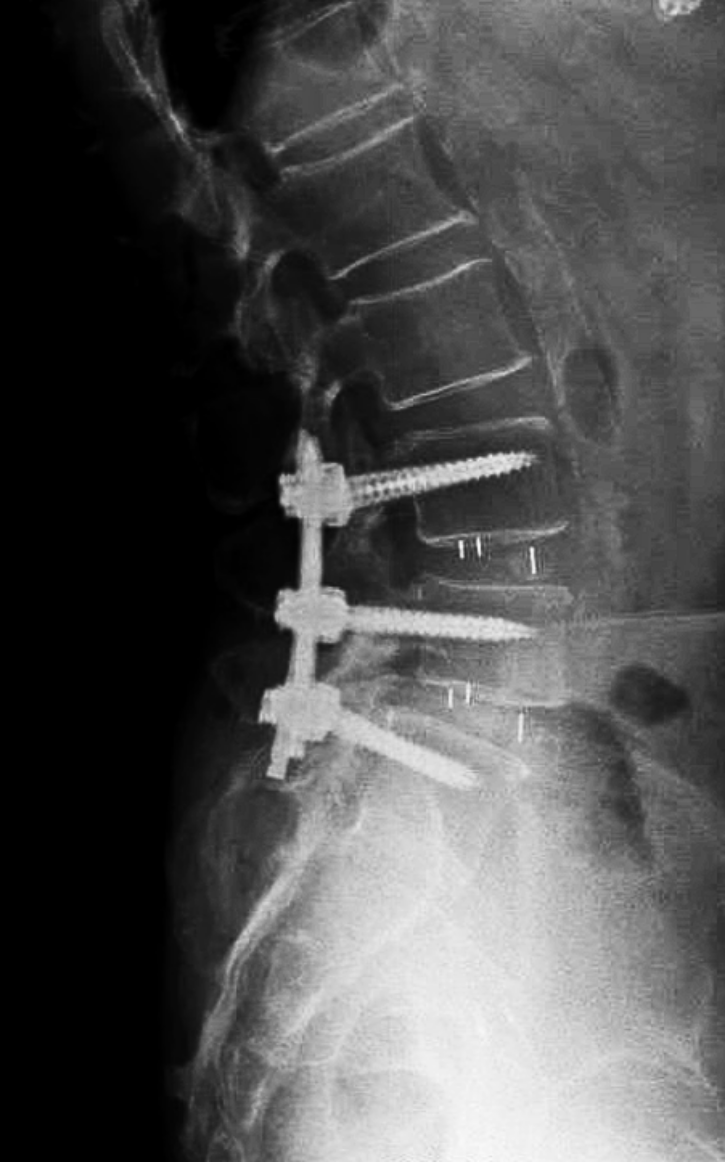

Minimally invasive lumbar fusion is an advanced surgical technique used to treat spinal instability, degenerative disc disease, or chronic pain by permanently joining two or more spinal bones in the lower back. Unlike traditional open lumbar fusion, which requires large incisions and significant muscle damage, Dr. Ramos uses smaller incisions and specialized instruments to access the spine with less disruption to surrounding structures. This results in several key advantages for patients, including reduced postoperative pain, minimal blood loss, and a lower risk of infection. Hospital stays are typically shorter, with Dr. Ramos usually discharging patients a day or two after surgery. The muscle-sparing nature of the procedure also helps preserve spinal strength and mobility, and patients often experience a faster return to normal activities. Because of its less invasive nature, this technique is particularly beneficial for older adults or those with other health conditions who may not tolerate open surgery well.